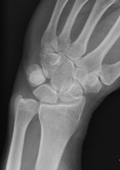

Im Zentrum für Orthopädie und Unfallchirurgie werden sämtliche Frakturen der Hand und des Handgelenks nach aktuellen Therapiealgorhythmen behandelt. Neben der gesamten Bandbreite der konservativen, nicht operativen Behandlungsmaßnahmen werden alle operativen Bruchstabilisierungen mittels aktueller Verfahren und Implantate versorgt.